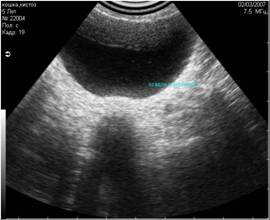

- вызванные плохим качеством выбривания кожи животного (Рис.3);

Рис3. Помехи, вызванные плохим выбриванием животного (продольные полосы слева). |